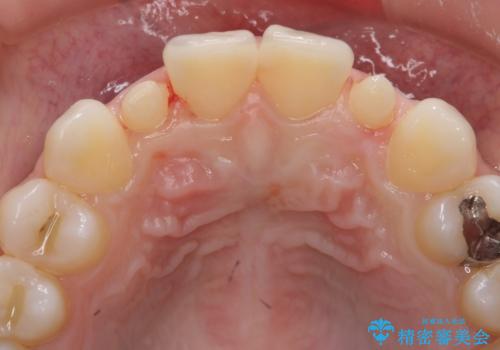

前から2番目の歯が小さく、細くとがった形になっていました。

大きくしようにも、幅が少ない上に、また、内側に入ってしまっているため、矯正治療で前歯を並べてからセラミックでかぶせることにしました。

先に矯正治療をすることで、下の前歯を内側に入れることができ、上の歯のセラミックの幅や厚みを取ることができました。